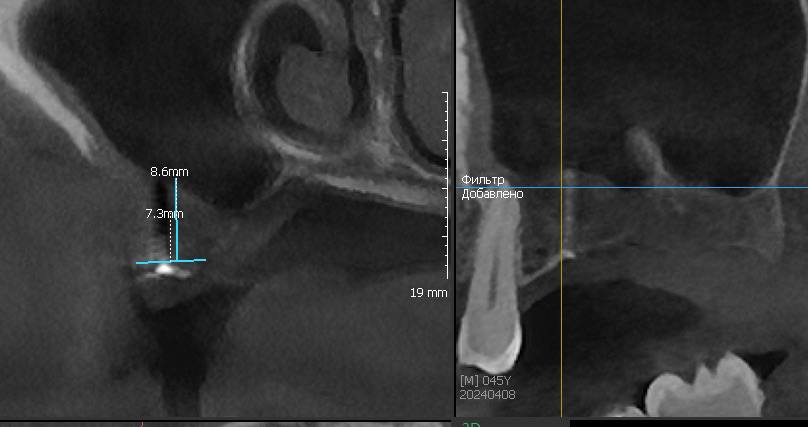

Открытый синус-лифтинг на губке и винте

Описание клинического случая:

• Открытый синус-лифтинг на губке и винте. Фиксация прямых мультиюнитов с усилием 30 Н/см

• После синус-лифтинга до установки имплантата прошло 3,5 месяца

Клинический случай Семерикова Дмитрия Юрьевича